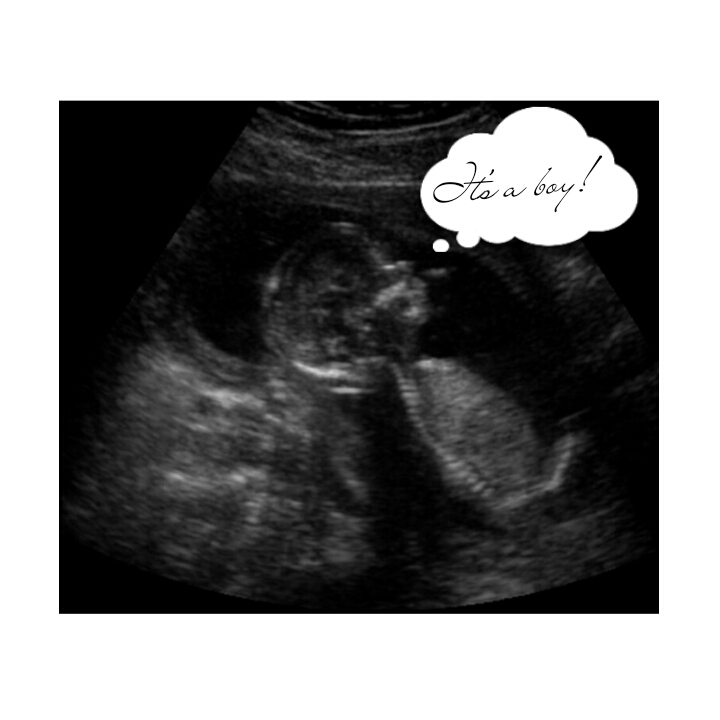

Сегодня мы с малышом побывали на первом скрининговом УЗИ. Срок 12+0 недель. У нас ожидается Маленький Принц

Я буду мамой мальчика:) У сыночка все хорошо. Развит на 13 полных недель, без ВПР. Носовая косточка и воротниковое пространство в норме:) Малыш очень стеснительный: все время уплывал от датчика, однако, врач попалась опытная - сумела его все-таки "поймать" и все замерить:)